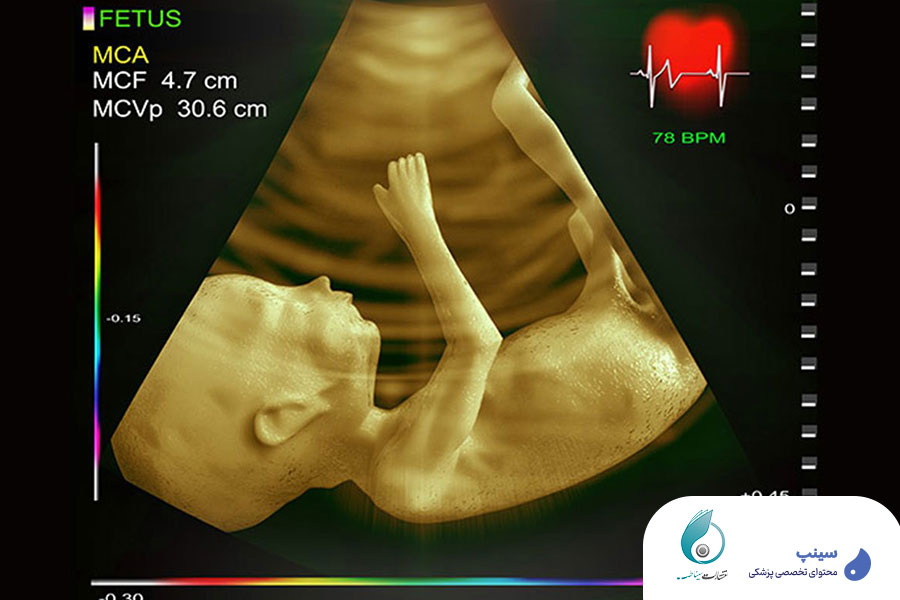

یکی از ویژگی های مهم این دوره، تمرکز بر روی یادگیری عملی و تصویری است. آموزش ها با استفاده از تصاویر واقعی سونوگرافی و نمونه های بالینی ارائه شده اند تا شرکت کنندگان بتوانند مباحث را به صورت کاربردی یاد بگیرند و در عمل از آن استفاده کنند.

روش‌های تصویربرداری پیشرفته در اکوکاردیوگرافی جنین: داپلر رنگی برای ارزیابی جهت و سرعت جریان خون در عروق و داخل قلب استفاده می‌شود و به شناسایی ناهنجاری‌های عروقی کمک می‌کند. تصویربرداری M-Mode برای بررسی حرکت دیواره‌های قلبی و ارزیابی دقیق‌تر عملکرد بطن‌ها و دهلیزها کاربرد دارد. استفاده از این تکنیک‌ها، دقت تشخیصی را افزایش می‌دهد و امکان ارزیابی دقیق عملکرد قلب جنین را فراهم می‌کند.